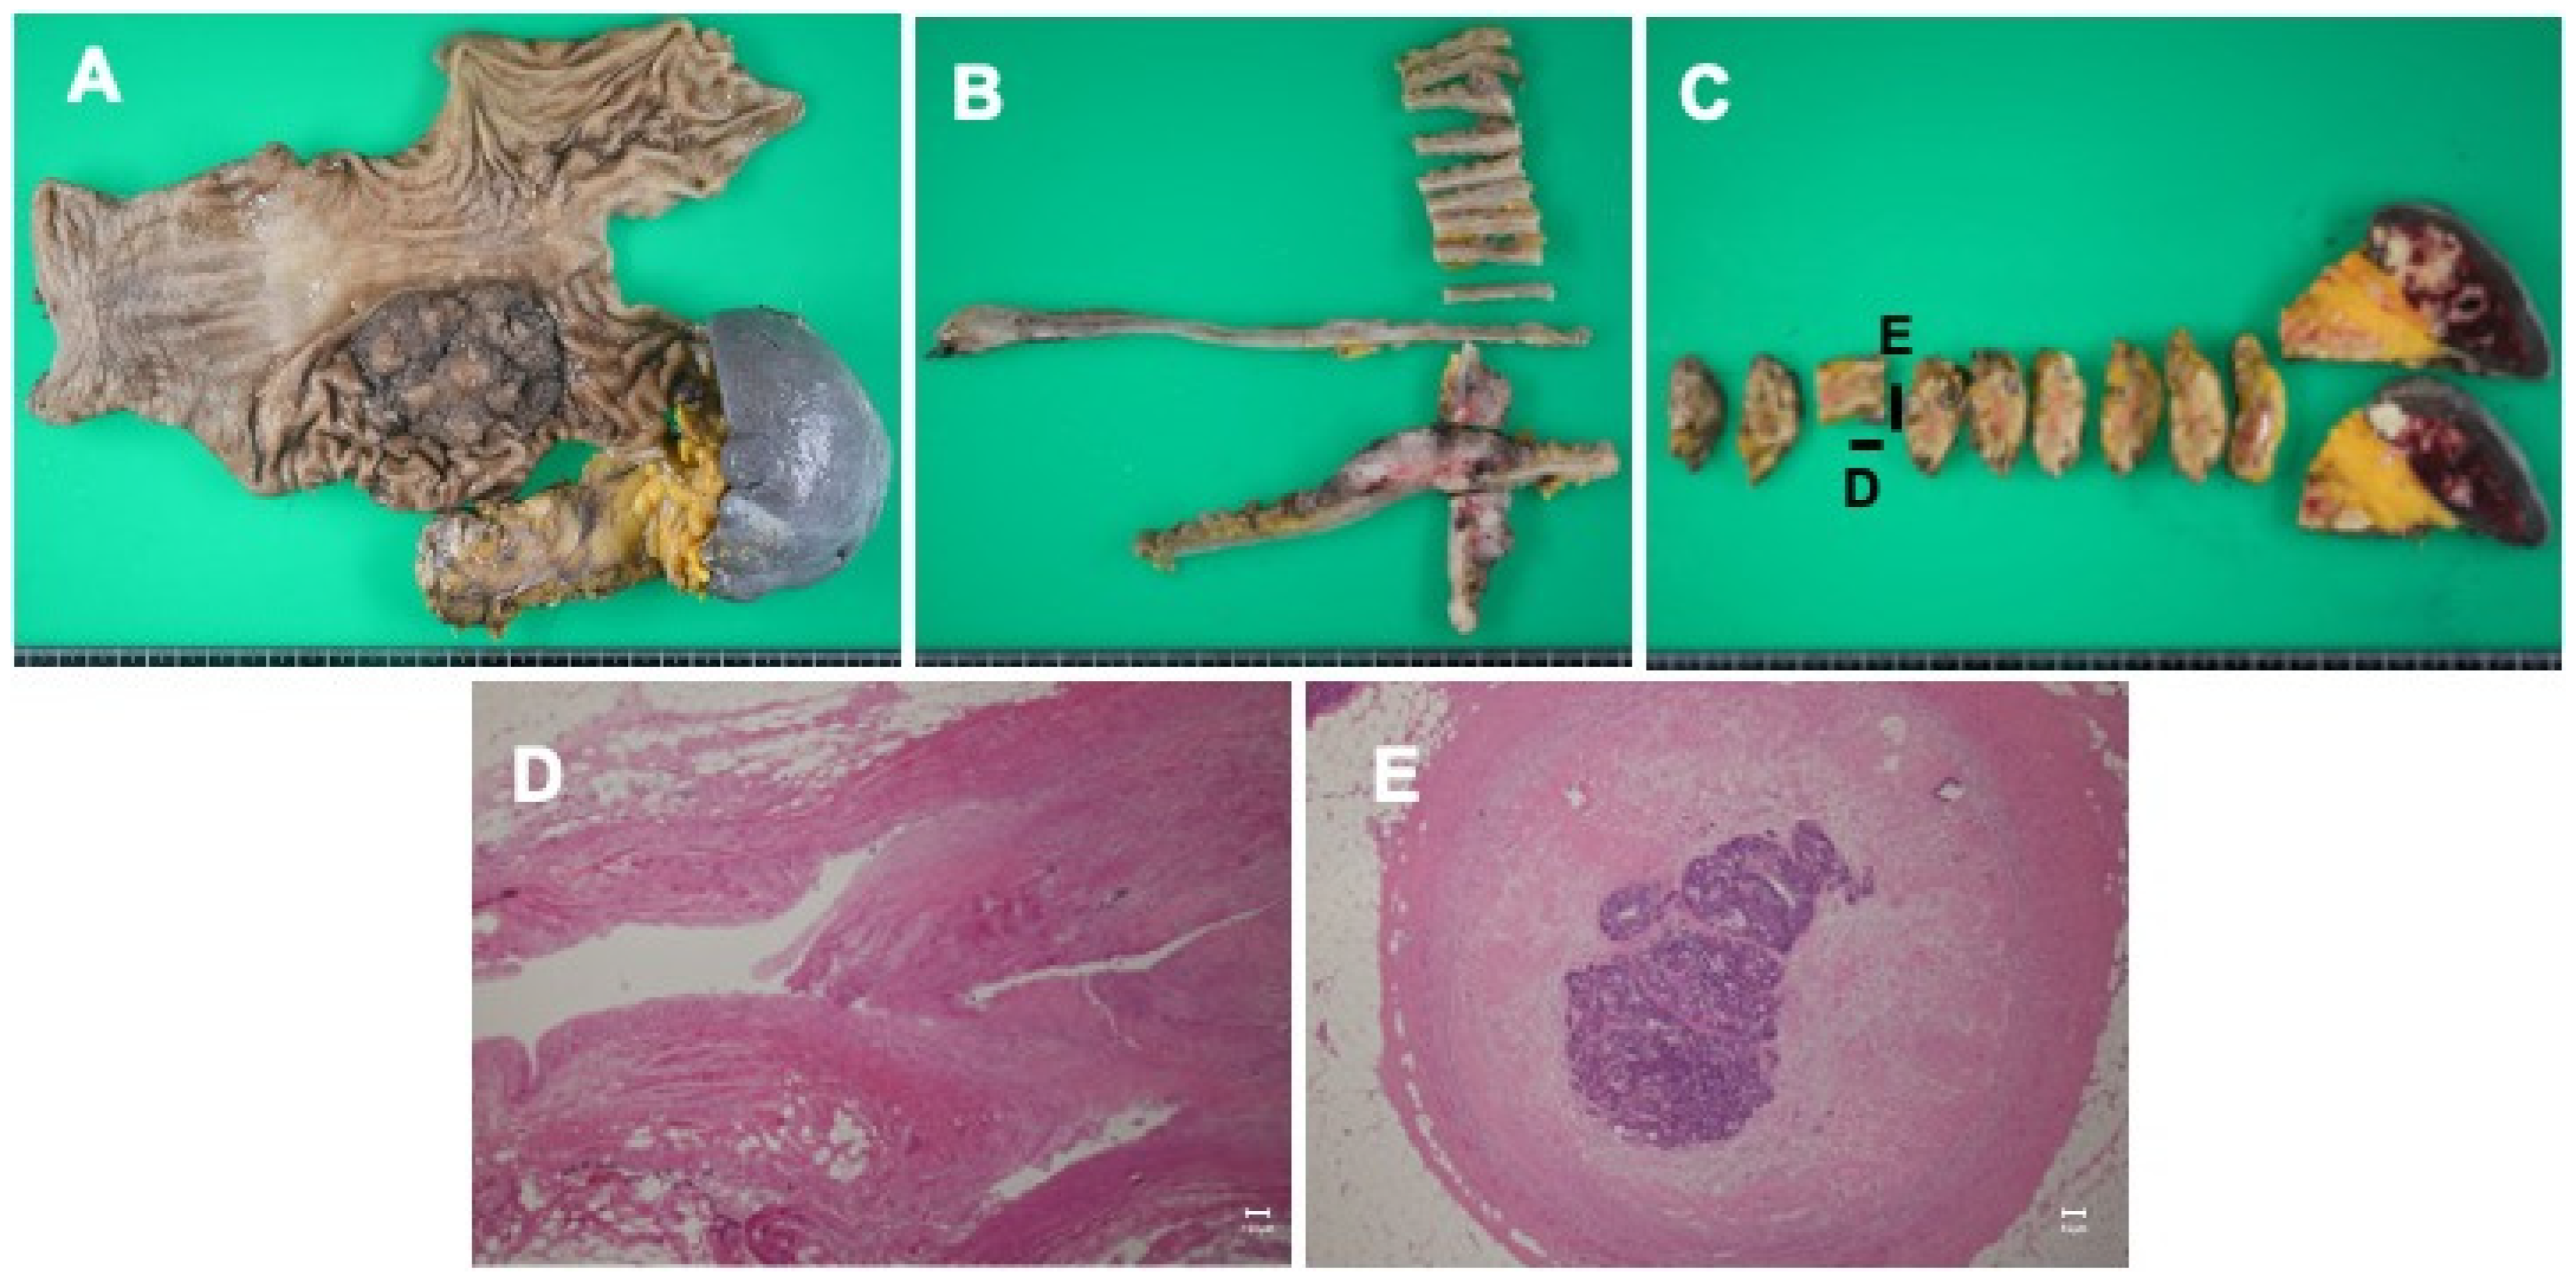

2. Case Presentation